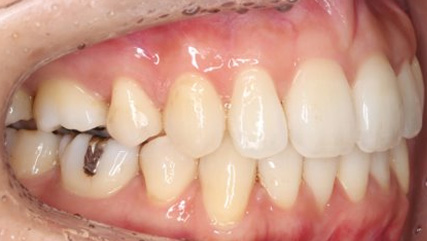

治療前

治療終了前

乱ぐい歯、でこぼこがとても酷い状態になります。歯が前後的に重なってしまっている、八重歯になっているなどがこのジャンルに入ります。

顎の大きさと歯の大きさのギャップが大きく、時には歯を抜かないと矯正治療ができない場合もあります。当院では治療期間が長くなるが抜かない治療方針など、一つの治療プランだけでなく、さまざまな可能性の治療方針を説明させて頂くよう心掛けております。こういった考え方はインフォームド・チョイスと言われ近年大切にされている考え方と言われております。